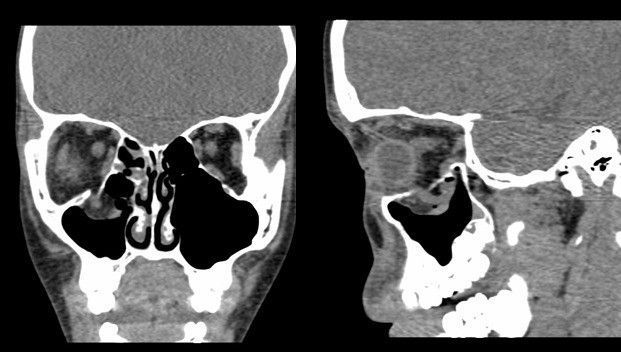

Компьютерная томограмма глазных орбит, на которой видно перелом дна правой глазницы с защемлением нижней прямой мышцы в верхнечелюстной пазухе.